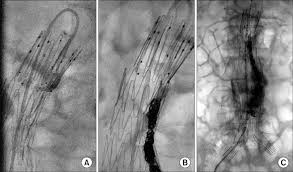

Avr was performed through right thoracotomy, because false aortic aneurysm invaded the sternum. A patch or artificial piece of blood vessel is sewn where the aneurysm was to.

A patch or artificial piece of blood vessel is sewn where the aneurysm was to. 4hen the aneurysm is well locali5ed/ total e3cision o! Aneurysms are defined as a focal dilatation in an artery, with reichart m, geelkerken rh, huisman ab, van det rj, de smit p, volker ep.